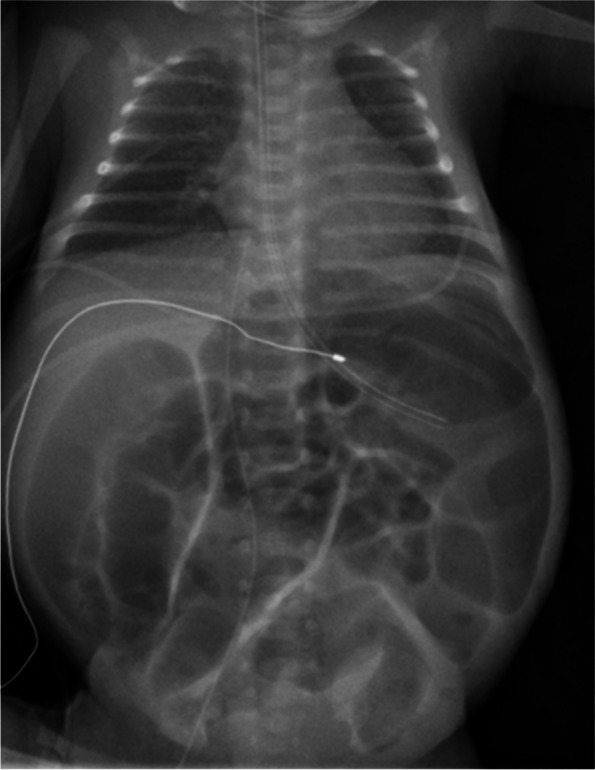

Case presentation: Here, we report the case of a preterm infant born at 30 + 2 weeks of gestation with a prenatal genetic diagnosis of mevalonate kinase deficiency presenting with intrauterine bowel dilatation, mild hydrops fetalis, and microcephaly. Laparotomy on the second day of life revealed intestinal obstruction necessitating partial ileum resection and ileostomy. The neonate had recurrent inflammatory reactions with elevated C-reactive protein levels, severe cholestasis, a progressive liver dysfunction, and an increasingly distended abdomen with subsequent respiratory insufficiency. Urinary mevalonic acid was highly elevated. The patient received anti-inflammatory therapy with prednisone and anakinra. Unfortunately, the patient died at the age of 77 days due to cardiorespiratory failure.

Conclusions: This case shows that intestinal obstruction with dilated fetal bowel loops can be an initially leading clinical symptom of severe mevalonate kinase deficiency. Diagnostics should be considered at an early stage, especially in the presence of other anomalies such as hydrops fetalis, growth restriction, or microcephaly. Data on the neonatal course of severe mevalonate kinase deficiency are still scarce and further studies are needed, particularly on treatment in neonates and young infants.